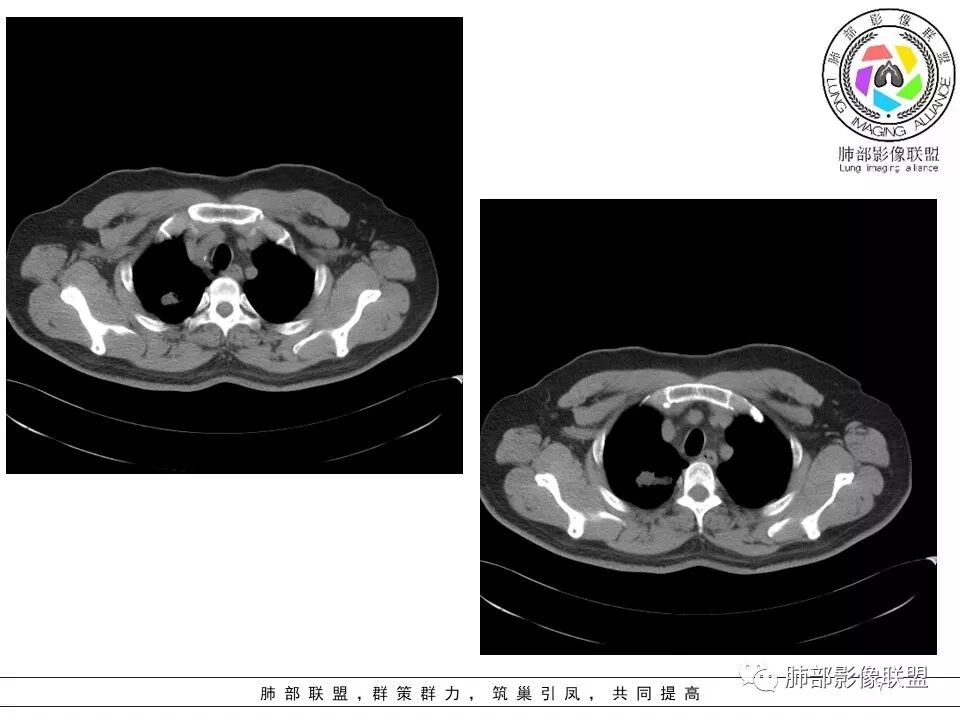

病史:男性,49岁,反复咳嗽月余,伴左胸痛;   影像:形态奇特,长毛刺,疑多灶,支气管阻塞不明显,毛刺不明显,纵膈窗密度不均,其内似见低密度,有凹陷,膨隆不除外,纵膈窗胸膜有点增厚。诊断:结核(右上肺)鉴别:不符合,无钙化,无胸腔积液;腺癌(无淋巴结)。处置:寻找结核相关检查,肿标,纤支镜,增强。

患者中年男性,主诉:咳嗽  胸痛。  胸CT:右肺上叶尖段占位,病灶位于支气管外,病灶周围部分区域可见毛玻璃影,病灶边缘不规则,部分区域可见平直,胸膜牵拉(无胸膜凹陷),柔软长毛刺,分叶,纵隔窗病灶没可见低密度区,左肺尖可见一点状病灶,病灶整体考虑良性疾病:感染性病变(结核?),感染后机化?。恶性病变待除外。

右肺上叶结节,边缘平直为主,病灶比较散,周周似乎有卫星病灶,边缘有胸膜牵拉,从粗到细,左肺尖奕有卫星灶,综合考虑结核。

晨读:患者中年男性,反复咳嗽1月余,伴左胸部疼痛1周就诊。胸部CT:右肺上叶尖后段不规则结节,见长毛刺、胸膜牵拉、条索影,周围见卫星灶。未见明显淋巴结肿大,符合结核病变。鉴别其他。但其病灶位于右肺,主诉左胸痛,是误写,还是?

影像,气管憩室,两肺尖都有病灶,长索条